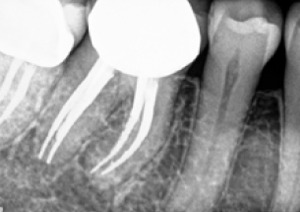

Fig. 1a. Periapical radiograph of tooth #30. (1)

Fig. 1b. Sagittal CBCT slice of tooth #30. (1) Note extensive periapical radiolucency